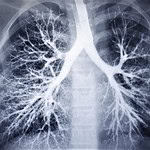

Ligos diagnozei svarbus ne vienas aspektas

Ligos diagnozei svarbūs ne tik paciento patiriami simptomai ir faktas apie jau galimai stebimas ligos sukeltas komplikacijas, bet ir žinios apie tai, kaip jo kvėpavimo takus ir plaučius veikia tabako dūmai, įvairios cheminės medžiagos, profesinės dulkės ir namų šildymo metu išsiskiriantys dūmai. Labai svarbu žinoti tai, kaip ir kiek laiko pacientas rūko, mat didžioji dalis (net iki 90 procentų ar daugiau) LOPL sergančių pacientų yra ilgą laiką rūkantys asmenys. Pacientas taip pat turėtų žinoti, ar šia liga kas nors sirgo/ serga jo šeimoje, nes genetinis faktorius LOPL diagnostikoje taip pat gali būti gana svarbus. Labai svarbią vietą LOPL diagnostikoje užima spirometrija. Taip pat būtina patvirtinti negrįžtamą kvėpavimo takų obstrukciją, atlikti kitus būtinus tyrimus ir parinkti tinkamiausią gydymą individualiu atveju.